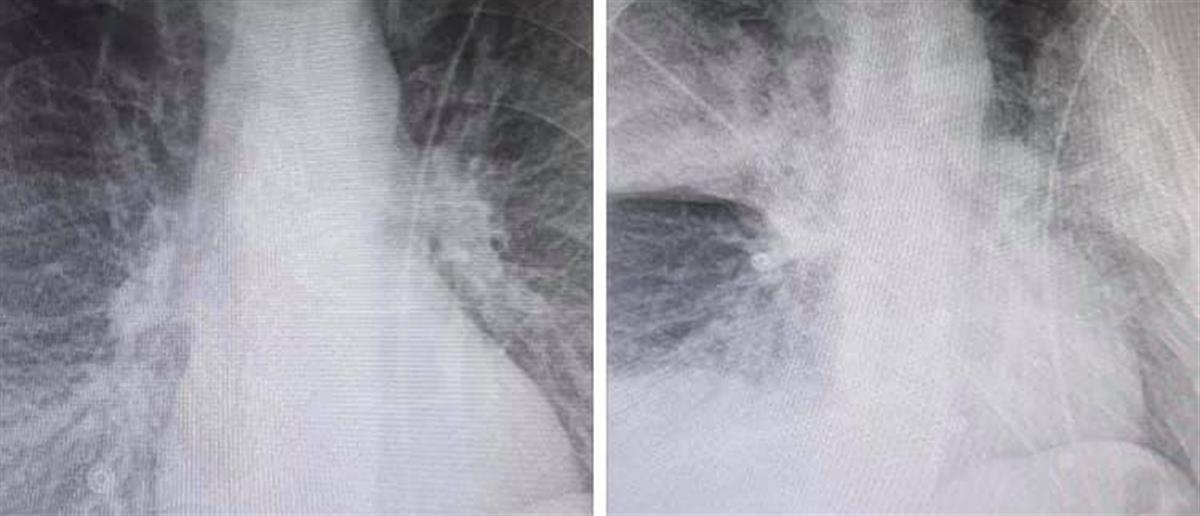

Αίσθηση αλλά και αντιδράσεις προκάλεσε η ανάρτηση του ακτινολόγου Μάνου Καρρά στο Facebook με δύο ακτινογραφίες, στις οποίες, σύμφωνα με τον ίδιο, αποτυπώνεται η ραγδαία επιδείνωση που προκαλεί ο κορονοϊός στους ασθενείς.

Ο γιατρός από το ΚΑΤ, ο οποίος έσπευσε να διαγράψει την ανάρτησή του λίγο μετά τις διαστάσεις που πήρε το θέμα και την αναπαραγωγή των φωτογραφιών από τα Μέσα Ενημερώσης, έκανε λόγο για την ραγδαία επιδείνωση της υγείας ενός 38χρονου καπνιστή και διαβητικού, μέσα σε μόλις 7,5 ώρες.

Σύμφωνα όμως με πληροφορίες, οι ακτινογραφίες δεν ανήκουν σε ασθενή με κορονοϊό, καθώς πρόκειται για υλικό του 2015!